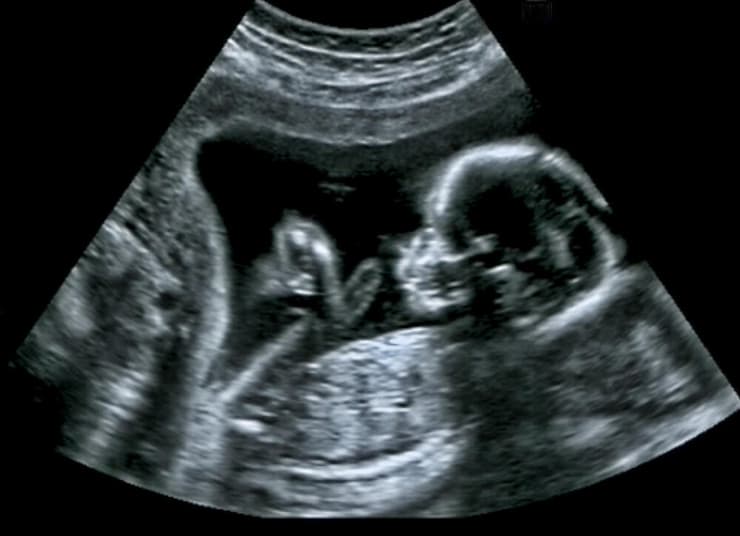

3 צפייה בגלריה

"חוק פעימות הלב" בארה"ב אוסר לבצע הפלות מרגע שניתן לזהות דופק עוברי

(צילום: Shutterstock)

העובר, שלו העניקה המשפחה את השם "צ'אנס" (Chance), ממשיך לגדול ומקבל סטרואידים ותזונה דרך צינור PICC. לפי דברי אימה של סמית', יש לו דופק חזק, הוא שוקל מעט מעל הממוצע לשלב ההיריון שבו הוא נמצא, וגפיו כבר התפתחו. עם זאת, הוא סובל מהצטברות נוזלים במוח, ולפי רופאיו ייתכן שייוולד עם פגיעות חמורות – עיוורון, שיתוק או מוות מיידי לאחר הלידה.